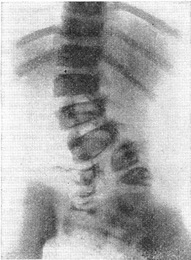

![]() Рис. 13. Альтернирующие клиноподібні полупозвонки. |

Бічні клиновидні хребці, або полупозвонки (рис. 12), відносяться до порівняно нередкому виду аномалій. Вони частіше бувають поодинокими або подвійними. В останньому випадку клиноподібні полупозвонки розташовані з протилежних сторін, і їх називають альтернирующими (рис. 13). Зрідка зустрічаються подвійні односторонні полупозвонки. Бічні клиноподібні полупозвонки є однією з причин вродженого сколіозу. Особливо несприятливі в цьому відношенні подвійні односторонні полупозвонки.